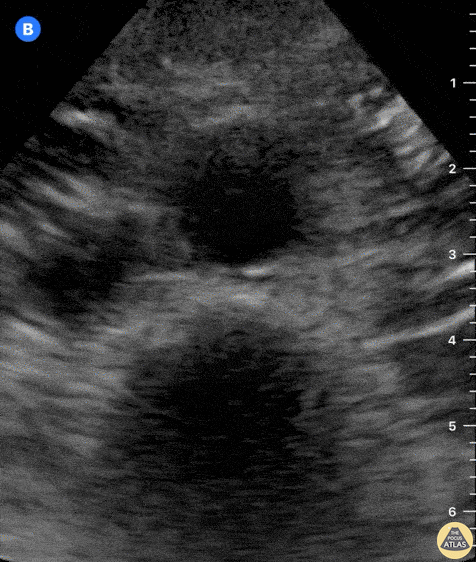

At the center of the screen, the distal aorta lies anterior to a vertebral body. Sliding the probe caudally reveals the emergence of the iliac arteries. This clip is taken at the umbilicus level, transverse to the body’s axis, and with the probe marker oriented to the patient’s right. Dr. Felipe Urriola P., Emergency Unit, Puerto Aysen Hospital, Chilean Patagonia.